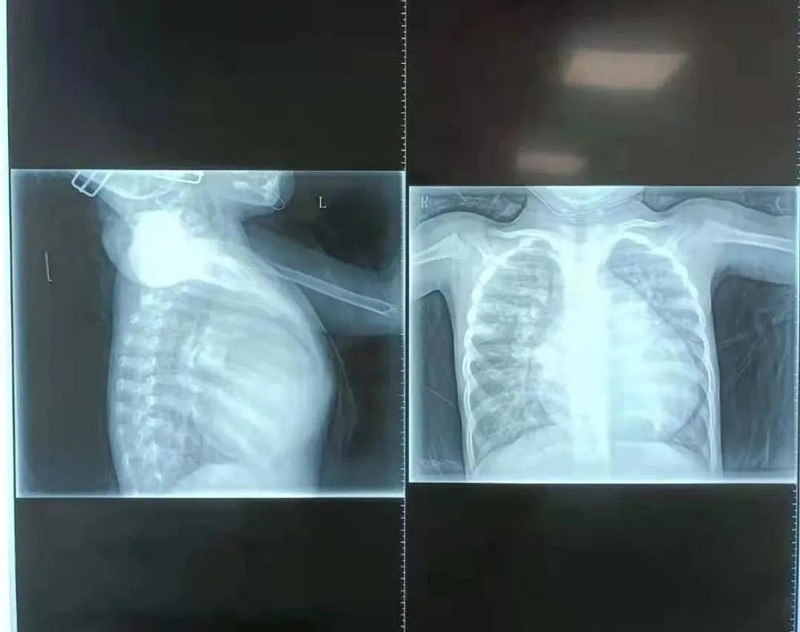

在a片网站 小儿心脏病诊疗中心,杨明远医生初见馨馨印象极为深刻,4岁的孩子体重仅10.5公斤,由于心脏变大,她的胸骨被挤压得明显向前凸起。检查发现,馨馨心脏室间隔有直径17mm的缺损,导致左心室血液一部分流向右心室。同时,馨馨出生后动脉导管就未闭合,导致血液从主动脉分流到肺动脉。为了维持全身用血,左心室需要不断增加“劳动量”,而全身血液加上分流到右心室的血液最终都回到左心室,造成左心室严重增大,左室疏末径达到50.1mm,比正常成年人(正常成人左室疏末径为35-50mm)还要大。杨明远医生说,在先天性心脏病中,室间隔缺损比较常见,但像馨馨的心脏畸形严重到如此程度、对身体影响如此大的实属少见。